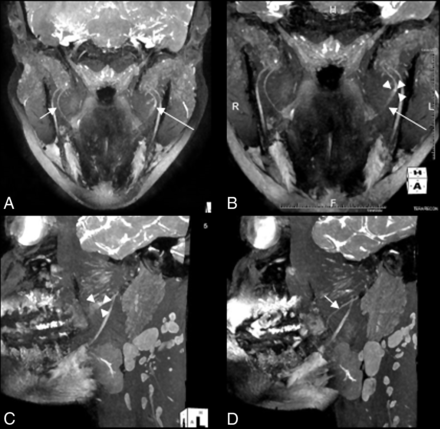

All scans were prospectively reported by an experienced, fellowship-trained radiologist as part of routine patient care. Neuropathy was determined based on various qualitative (increased nerve T2 signal and perineural fibrosis) and quantitative (caliber alterations) criteria. Findings were confirmed on multiple sequences (T1, T2 fat-suppressed, PSIF, and DTI). A Sunderland classification was given to each nerve injury by using the qualitative criteria as described in Table 2 (Figs 1 and 2). When a single class could not be determined based on MRN (eg, report stated “Sunderland class III/IV or class IV/V injury”), the case was classified as indeterminate (On-line Table 2). All information was extracted from the formal reports and recorded for comparison with clinical NST and surgical findings.

A and B, MIP 3D coronal PSIF images show a hyperintense left LN (long arrow) with a 3-mm neuroma in continuity (demarcated by 3 arrowheads) compatible with class IV injury. C and D, Sagittal reconstructions show the abnormal left LN neuroma (demarcated by 3 arrowheads) compared with a normal right LN (short arrow).